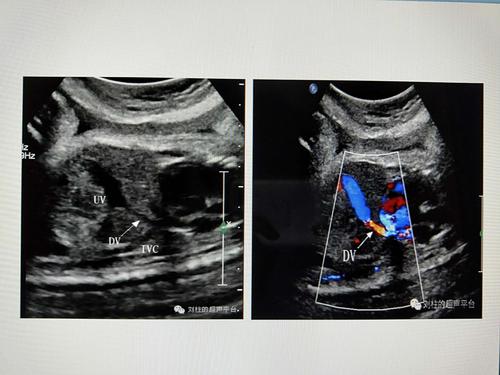

胎儿静脉导管超声图像

胎儿静脉导管超声图像,胎儿动脉导管超声图解

胎儿静脉导管超声切面

胎儿静脉导管解剖

胎儿静脉导管超声图片

静脉导管超声图

胎儿静脉导管频谱

胎儿静脉导管血流频谱